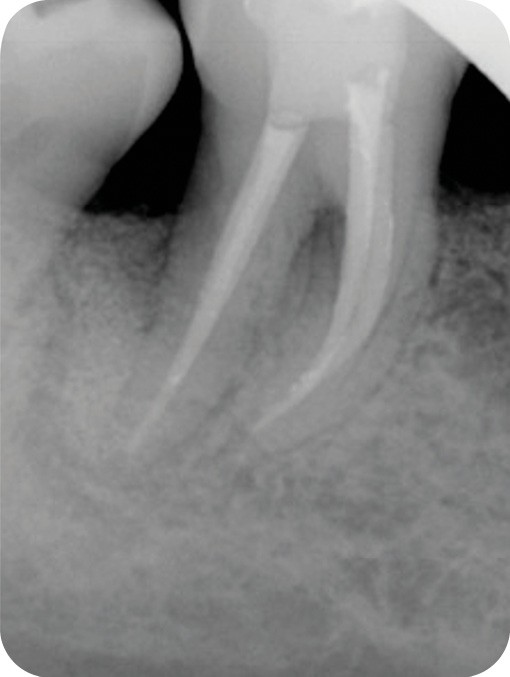

Radiographie contrôle à 4 ans |

2. Exemple de prise en charge d’une lésion endo-parodontale sans atteinte de l’intégrité radiculaire, chez un patient atteint de parodontite, de grade 3 (poche parodontale profonde sur plus d’une surface dentaire). Le traitement endodontique est réalisé dans un premier temps. Après réévaluation à 6 mois, une contention a été placée et une thérapeutique parodontale complémentaire a pu être réalisée (surfaçage et mise en place de matériaux de comblement). La maintenance parodontale est effectuée régulièrement afin de maintenir le résultat obtenu.